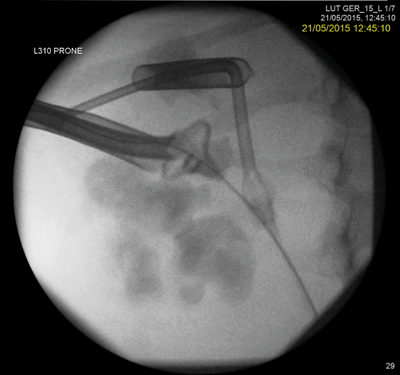

A rendezvous procedure was performed in the supine oblique position. The radiologist punctured the non-dilated kidney, feeding a wire antegradely to the bladder, allowing subsequent ureteroscopy and stone clearance.

Multiple failed attempts at ureteroscopic or percutaneous access do not help the doctor-patient relationship and can potentially put the patient at unnecessary risk when comorbidity is present. The Rendezvous procedure should not be forgotten as a ‘one stop’ method of dealing with ureteric obstruction. A combined antegrade and retrograde approach may decrease the number of separate interventions required to successfully cross a difficult stricture.